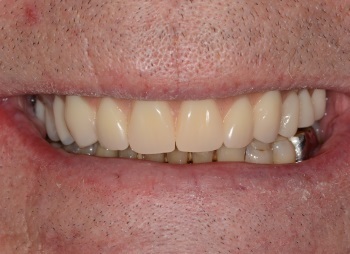

Vue satisfaisante du sourire du patient.